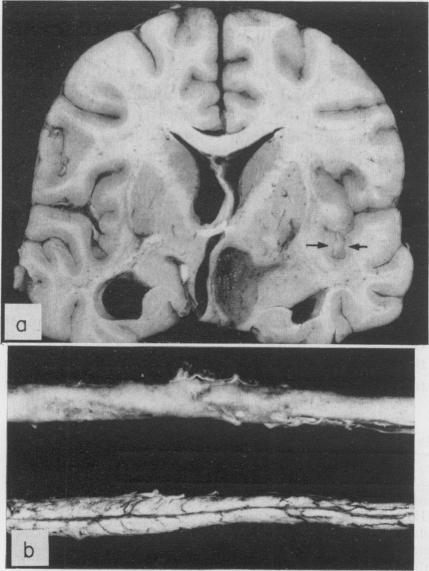

The clinical and pathological features of 63 cases of post-mortem-proved diffuse infiltration of the leptomeninges by tumour are presented. A wide variety of tumours of the nervous system, both primary and secondary, was found to give rise to such involvement, with adenocarcinoma having a particular propensity to behave in this manner. Dysfunction of cranial and spinal nerves, a confusional state and headache were prominent clinical features. Examination of the cerebro-spinal fluid was found to be less useful diagnostically in cases of primary tumours of the nervous system with leptomeningeal involvement than in cases of diffuse infiltration of the meninges by carcinoma.